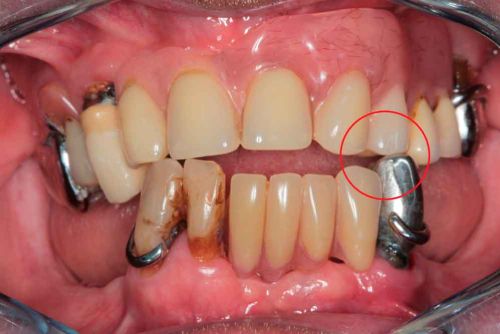

Photo - Situation intra-orale

Modèles 3D - Occlusion obtenue par la caméra intra-orale